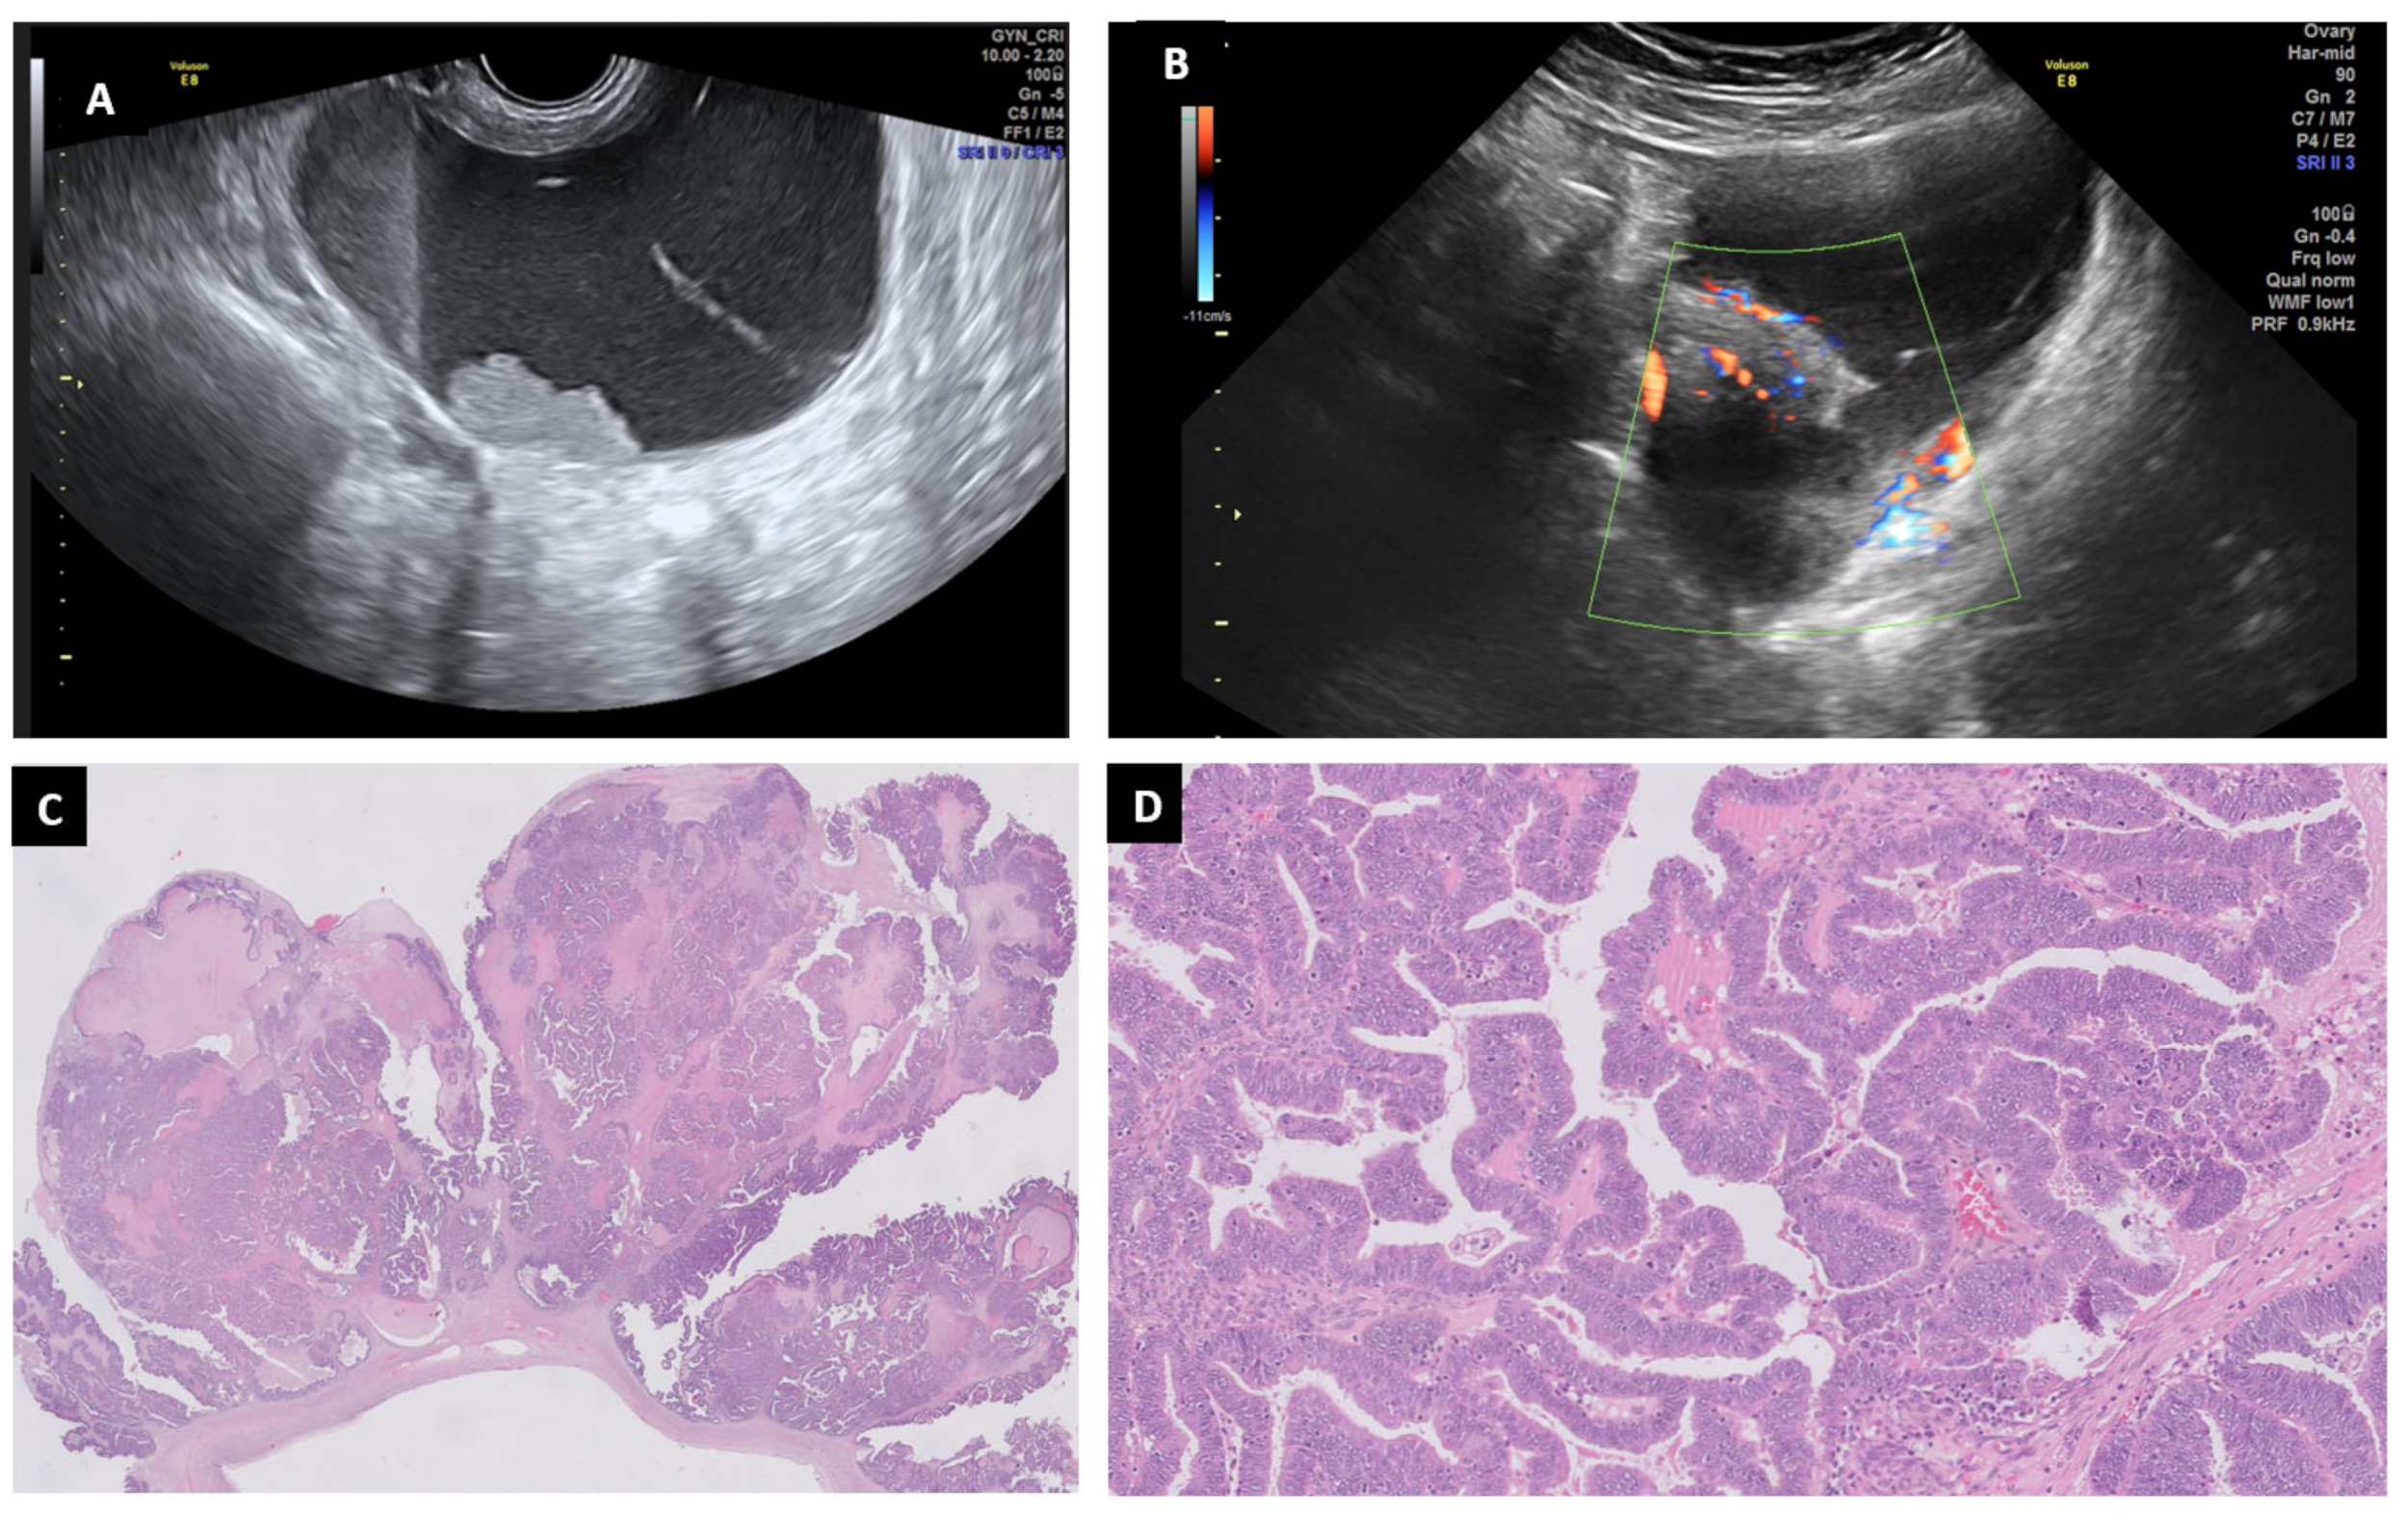

6.8. Serous Carcinoma